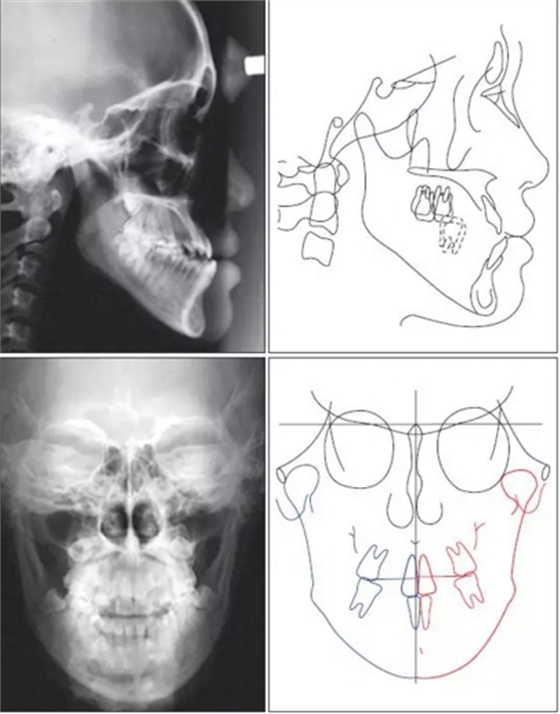

患者側(cè)貌為凹面型。頭側(cè)分析顯示,患者為骨性III類,下頜前突(Pog to N-perpendicular, 10.8 mm; ANB, −5.8°),上切牙前傾(upperocclusal plane to upper incisors, 51.0°),切牙后傾(lower occlusal plane to lower incisors, 80.5°),合平面平坦(upper occlusal plane to FH, 7.5°)??趦?nèi)檢查,患者為III類咬合關(guān)系,前牙和后牙反合,上頜第二磨牙伸長(zhǎng)。全景片顯示,第三磨牙阻生。頭顱正位片顯示由于右磨牙過(guò)度萌出導(dǎo)致合平面傾斜?;颊呦骂M向左偏斜,下牙列中線左偏。由于牙槽橫向補(bǔ)償,上切牙向左側(cè)傾斜。

根據(jù)上述發(fā)現(xiàn),患者被診斷為骨性III類錯(cuò)頜畸形,下頜前突,面部不對(duì)稱。